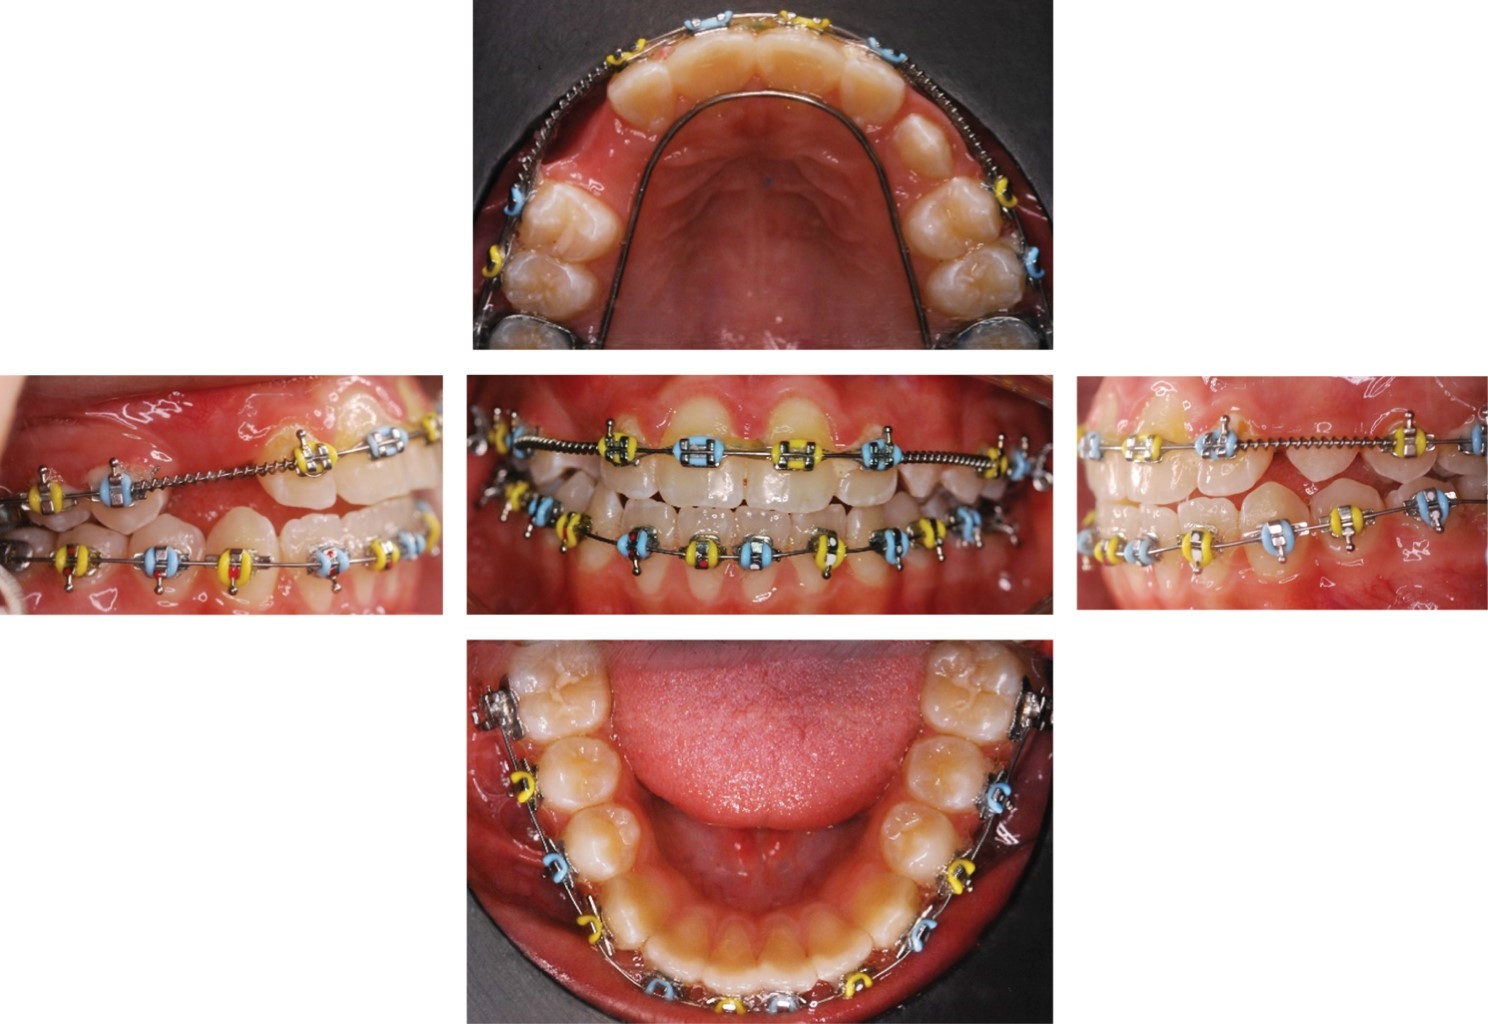

Se inició el tratamiento con la cementación del Hass y arco lingual como se muestra en la Figura 4, se decidió retirar Hass durante dos semanas, debido a que el paciente presentó una tumefacción en zona de tornillo expansor. Se continuó con su uso durante dos semanas más y a los cuatro meses se retiró Hass y se colocó arco palatino con espolones para controlar la proyección lingual (Figura 5).

A los siete meses se realizó colocación de aparatología Alexander slot 0.018" en superior y se suspendió uso de arco lingual inferior.

Posteriormente, se cementaron brackets de los órganos dentales #14 y #15 con resorte para distalizar el órgano dental #14, se consolidó con ligadura metálica, y se cementaron brackets de #24 y #25 como se muestra en la Figura 6. A los 11 meses se logró espacio para los caninos superiores y se realizó la colocación de aparatología inferior de 6-6 con arco 0.016" NITI SE y colocación del bracket del órgano dental #23. El órgano dental #13 erupcionó sólo de la cúspide y se decide colocar un botón con hilo elástico al arco para traccionarlo junto con el uso de un elástico Delta izquierdo del órgano dental #23 a los órganos dentales #33 y #34 de de 3.5 oz. Cuando se logró la alineación y nivelación a los 32 meses se colocaron arcos 0.016" × 0.022" SS y del elástico en caja anterior ¼ de 6 oz.

Figura 4

Figura 5

Figura 6